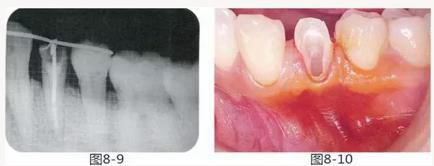

圖8-9 同時期的X光照片。牙槽骨無變化。

圖8-10 約一個月后,進(jìn)行牙周外科治療之前的狀態(tài)。附著齦較少。